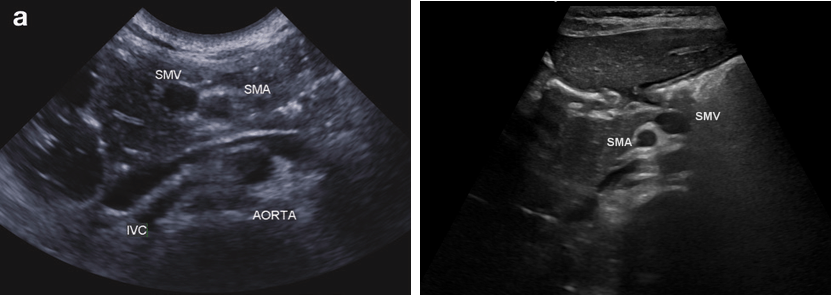

초음파: SMA/SMV 위치 역전

좌: 정상 소견 (V우측, A좌측)

우: malrotation 환아 (A우측, V좌측)